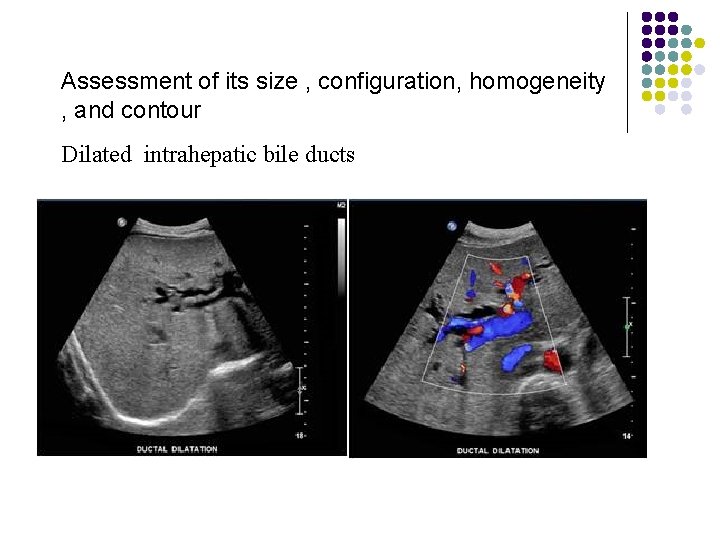

Assessment of its size , configuration, homogeneity , and contour Dilated intrahepatic bile ducts